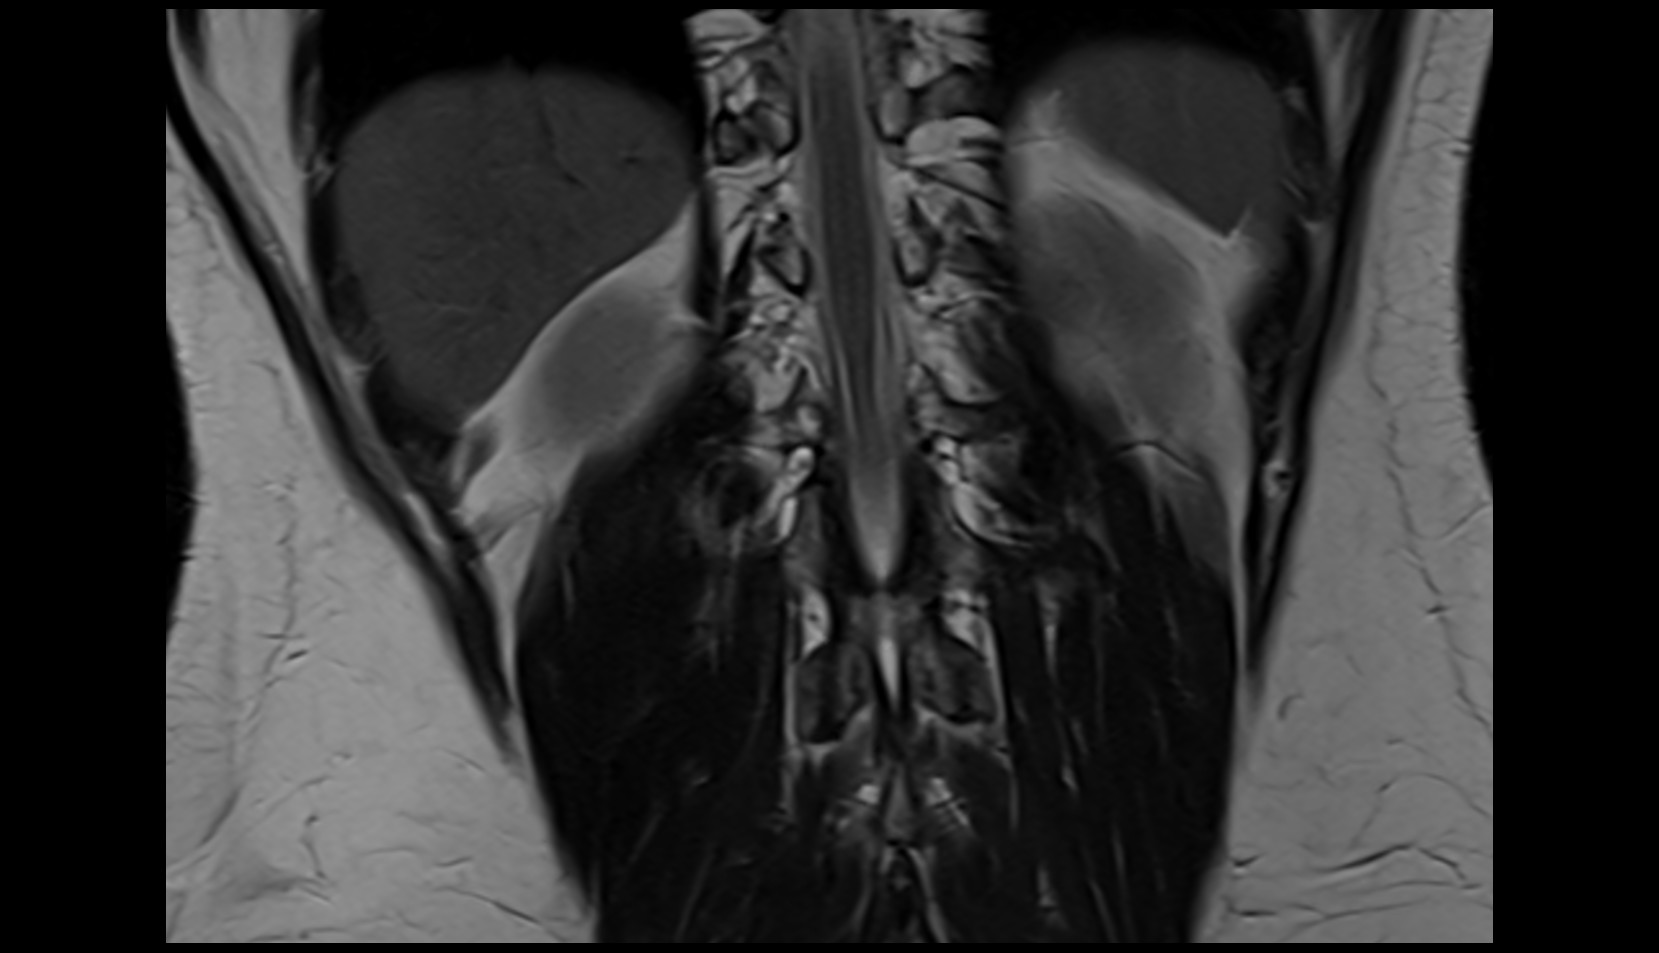

- Cauda equina

- Conus medullaris

- Erector spinae muscles